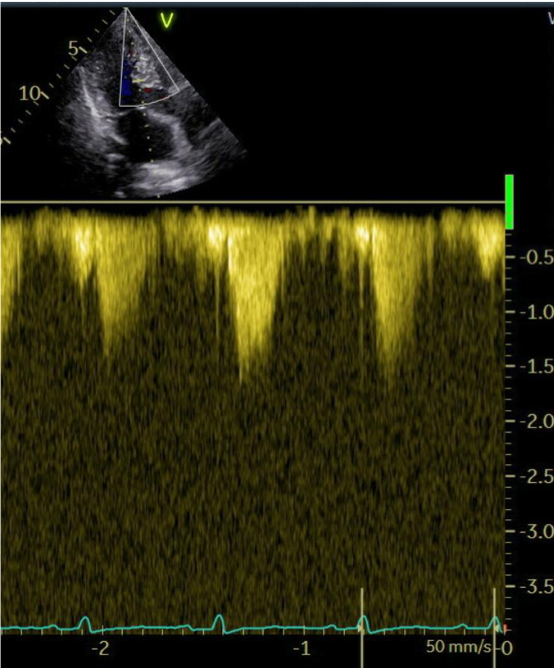

The patient was followed up every 4 weeks. A constant improvement of symptoms, echocardiographic findings and laboratory values was observed throughout the therapy. At the 6-month follow-up, dyspnea was classified as NYHA-Class II, the maximum LVOT gradient was 11 mmHg (Image 1b), and NT-proBNP notably decreased compared to baseline (202 ng/L).The systolic function of the left ventricle remained within the normal range. Seven months following the initiation of therapy with a myosin inhibitor, genetic testing revealed a positive result for a mutation consistent with Noonan Syndrome.